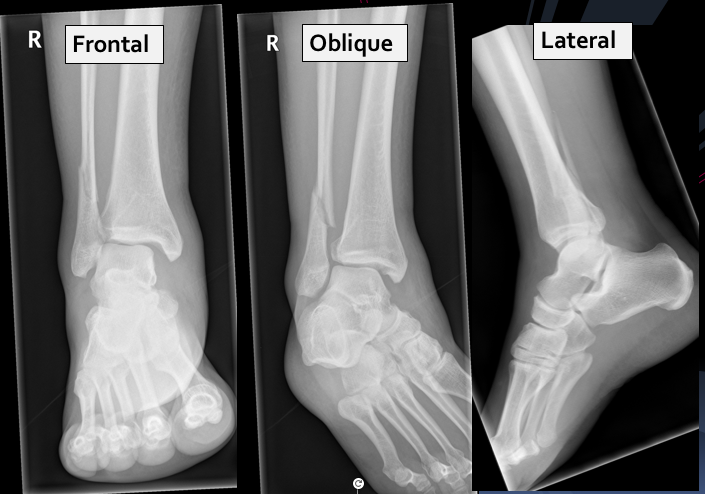

A 25 year old man presented to the ED with right ankle pain after a fall.

He was struggling to walk. His ankle was swollen and tender on examination. Movement was limited due to pain.

What can you see? What injuries are present?